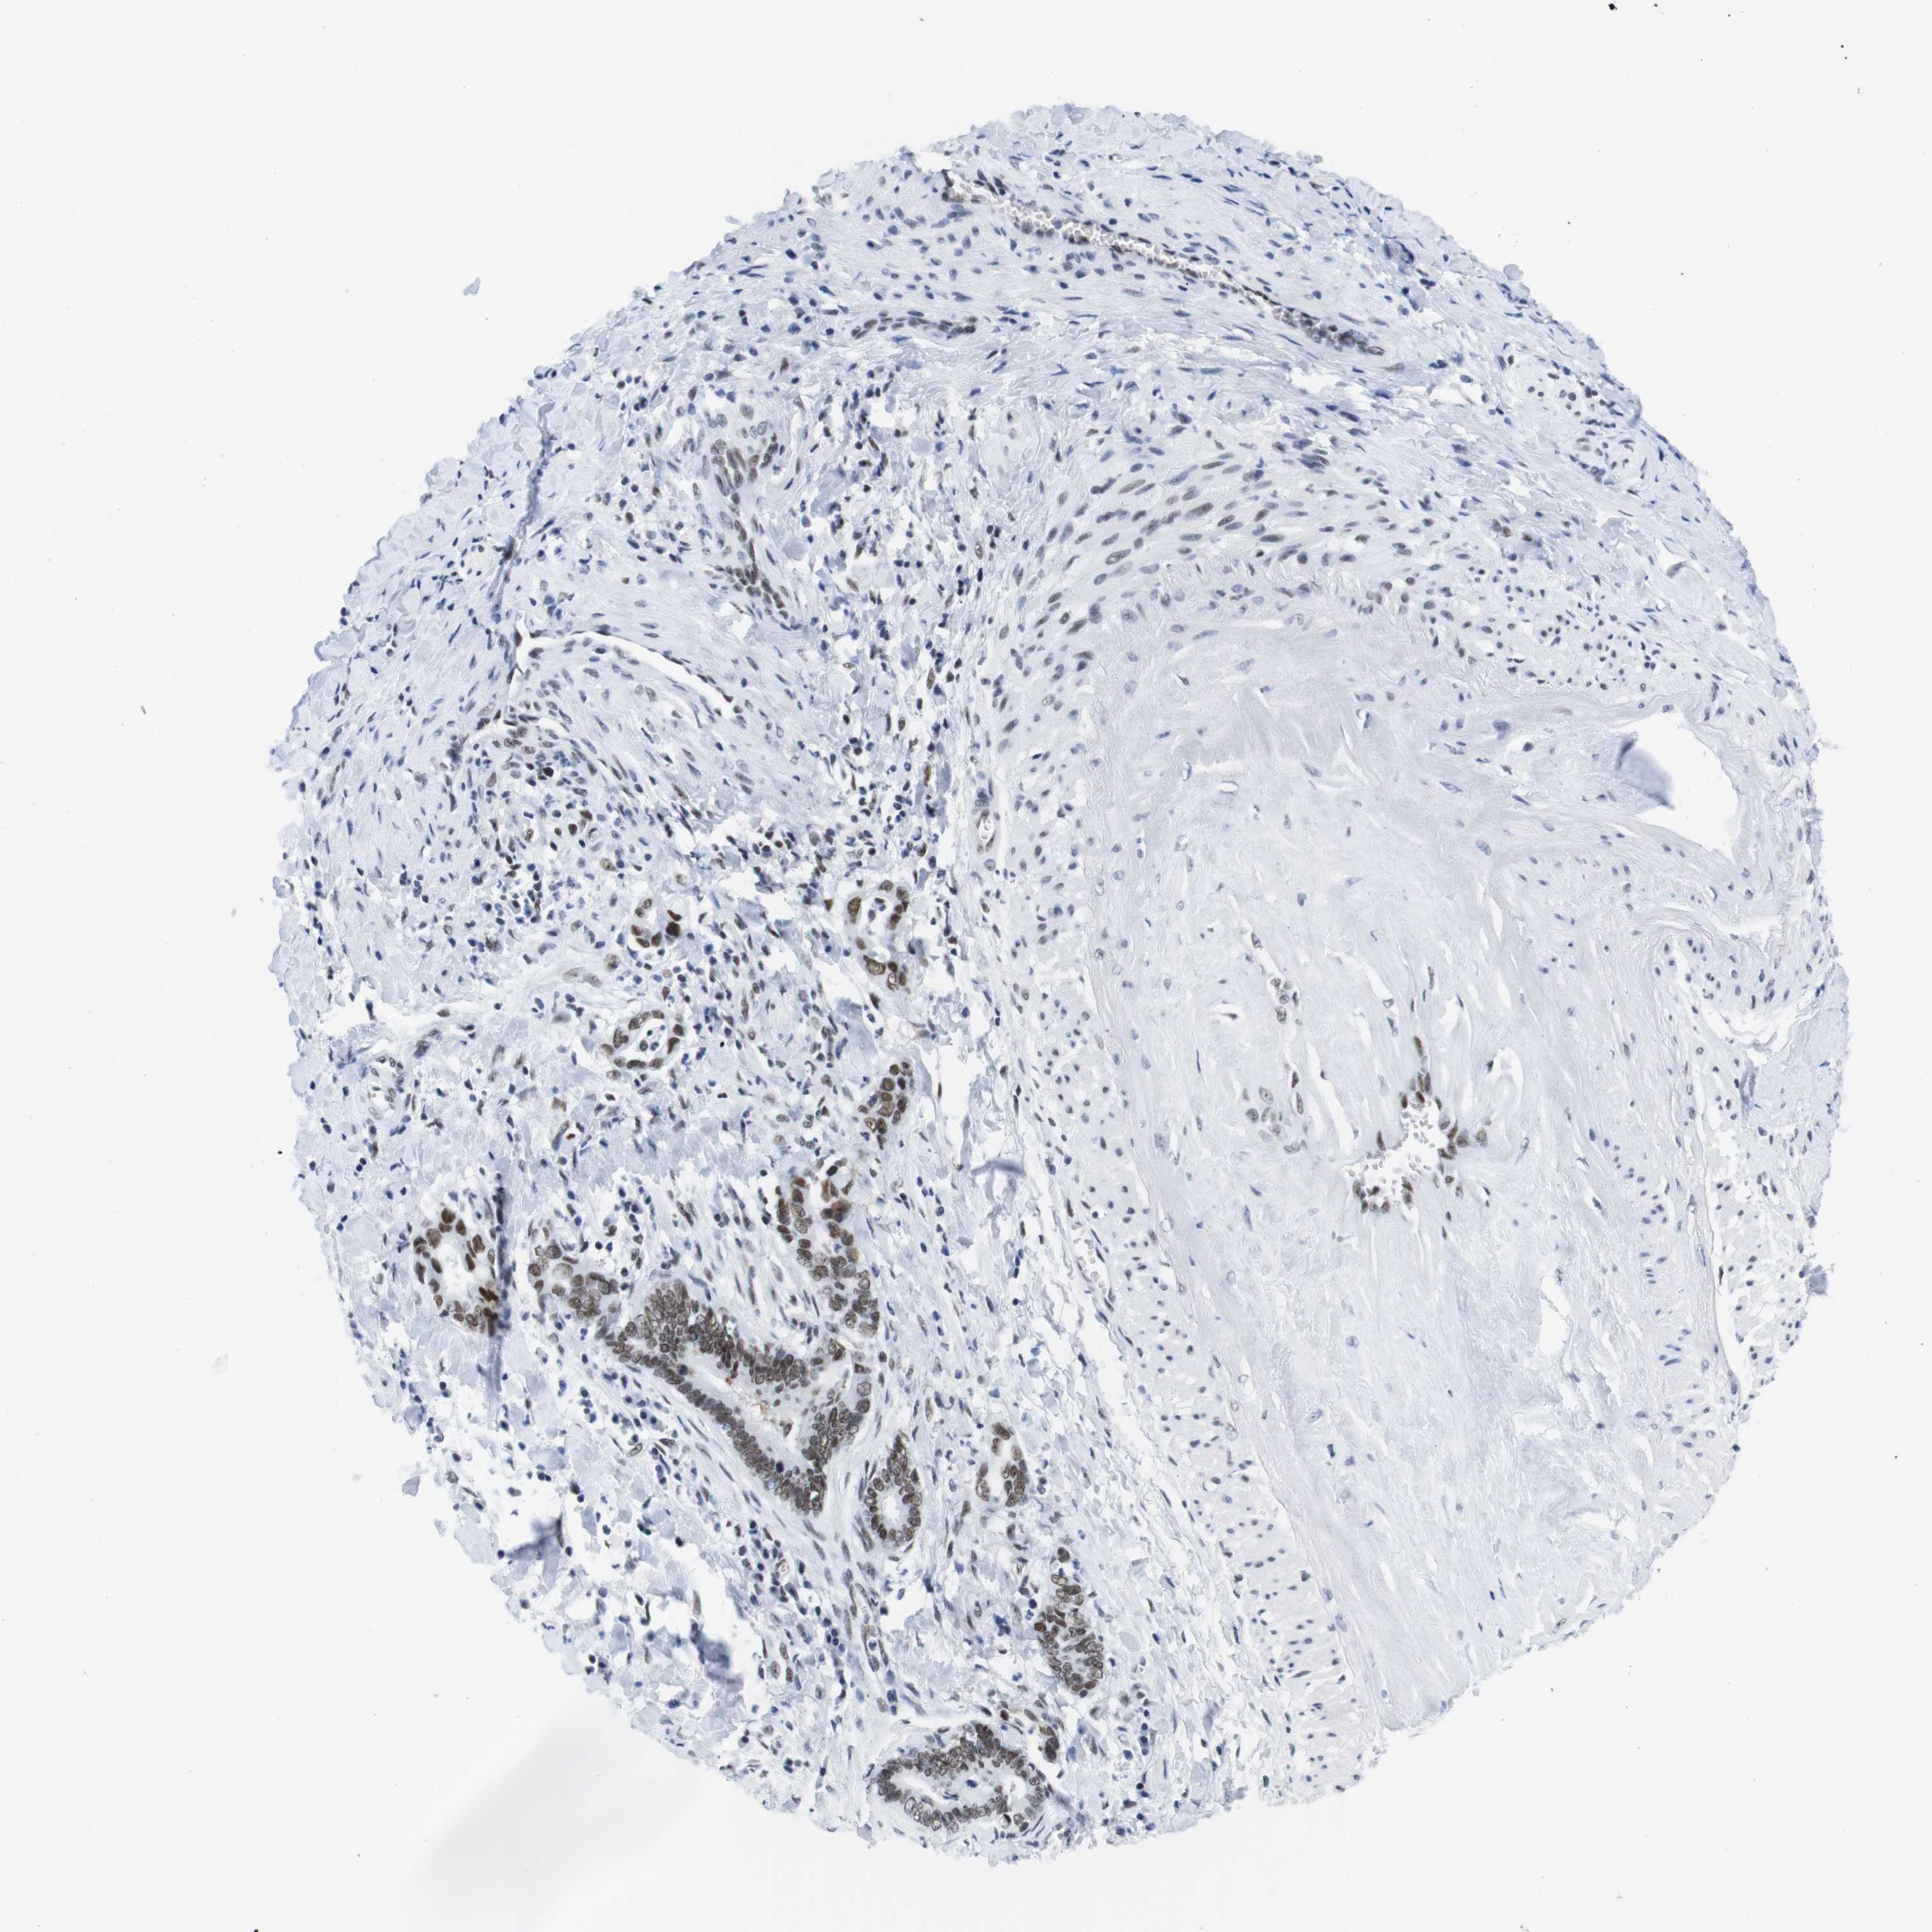

CERVICAL CANCER - Protein expressioni

A mouse-over function shows sample information and annotation data. Click on an image to view it in a full screen mode. Samples can be filtered based on level of antibody staining by selecting one or several of the following categories: high, medium, low and not detected. The assay and annotation is described here.

Note that samples used for immunohistochemistry by the Human Protein Atlas do not correspond to samples in the TCGA dataset.

Antibody stainingi

Antibody staining in the annotated cell types in the current human tissue is reported as not detected, low, medium, or high, based on conventional immunohistochemistry profiling in selected tissues. This score is based on the combination of the staining intensity and fraction of stained cells.

Each image is clickable and will lead to virtual microscopy that enables deeper exploration of all samples and also displays staining intensity scores, fraction scores and subcellular localization as well as patient and tissue information for each sample.

Antibody HPA002134

Antibody CAB016293

Staining

High

Medium

Low

Not detected

Intensity

Strong

Moderate

Weak

Negative

Quantity

>75%

75%-25%

<25%

None

Location

Nuclear

Cytoplasmic/membranous

Cytoplasmic/membranous,nuclear

Squamous cell carcinoma, NOS

Adenocarcinoma, NOS